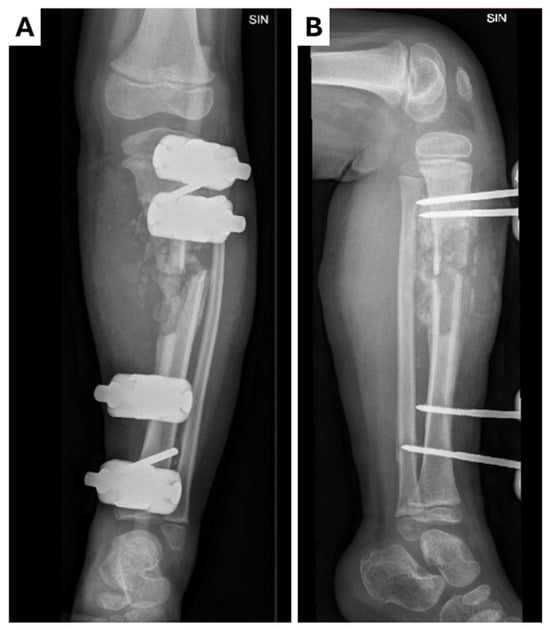

The patient underwent scheduled admission one month later for follow-up lower leg reconstruction: osteotomy, osteonecretomy, pseudoarthrosis plasty with a vascularized fibular graft, and osteosynthesis with a locking plate (Figure 4). The patient was prescribed clindamycin. The next day, the patient developed a fever (T 40 °C) with swelling, redness, and pain in the leg (CRP 119 mg/L). An acute surgical revision was performed. The wound was clean, and no purulent discharge, no hematoma, and no significant signs of infection were observed. Cefuroxime was added and the patient was admitted to the ICU. However, the fever did not subside over the next 24 h, so the antibiotic was changed to piperacillin/tazobactam. The fever gradually resolved over the next two days and the patient was transferred back to the ward. A decompression incision was made later in the day. There was no discharge from the wound and no signs of infection. The removed cast was reapplied to the leg. A week later, the wound site was surgically closed and monitored for one week before discharge. Instructions were given to continue cast immobilization for an additional eight weeks.

Figure 4.

Radiological examinations of the left leg showing chronic osteomyletic changes in the tibial diaphysis in the (A) X-ray anterior–posterior projection; (B) X-ray lateral projection. A proximal–distal osteotomy of the tibia was performed, resecting the pseudoarthrosis and exposing the bone surfaces. A proximal–distal osteotomy of the fibula was also performed, along with the rotation of the bone fragments to place them in the defect around the pseudarthrosis. Osteosynthesis was performed with a locked plate and five screws while maintaining the axis of the bone. A sterile aseptic dressing and plaster cast were applied.